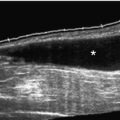

Magnetic resonance imaging (MRI) should be the next test obtained for patients with a high clinical likelihood of labral disease. There is controversy as to whether high-resolution non–contrast-enhanced MRI or magnetic resonance arthrography is the “gold standard” for diagnosis of SLAP lesions [19,20]. With the high rate of concomitant shoulder injuries, MRI is helpful in showing both intra-articular and extra-articular pathologic changes within the soft tissues. Positioning of the arm in external rotation or abduction and external rotation can improve the ability to accurately diagnose these lesions [21,22]. Computed tomographic arthrography may also be used if MRI is contraindicated, but it is less sensitive to other soft tissue disease. Ultrasound may be useful to visualize concomitant disease, such as tears of the rotator cuff and paralabral cyst, but it has poor visualization of the labrum.